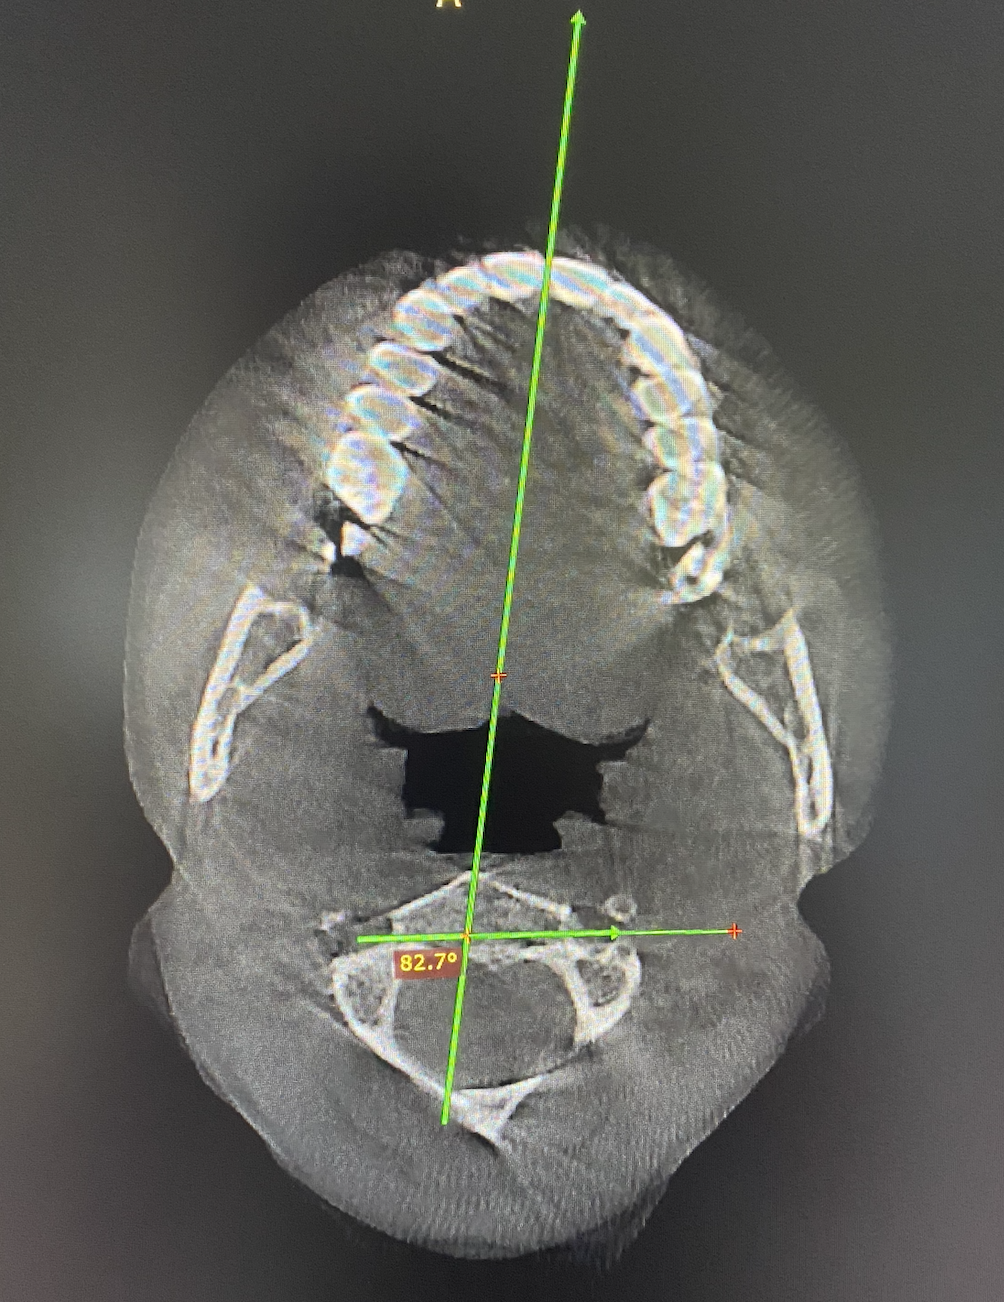

Cone Beam CT (CBCT) to analyze upper cervical structure with precision